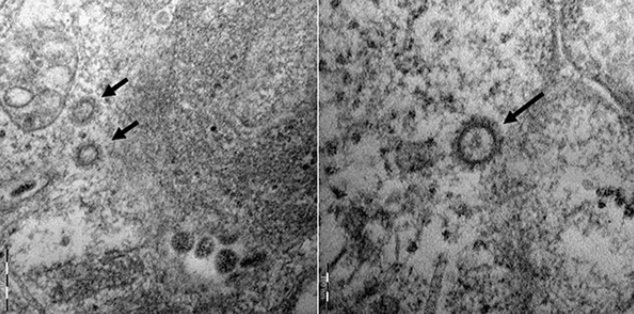

호주 모니쉬대학 생의학발견연구소의 카일리 왜그스태프 박사는 세포 배양된 코로나19 바이러스가 이버멕틴에 노출되자 48시간 안에 모든 유전물질이 소멸됐다는 실험 결과를 발표했다고 사이언스 데일리가 지난 4일 보도했다.

단 한 번 투여된 용량에도 24시간 후 코로나19 바이러스의 RNA가 상당 부분 줄어들었고 48시간이 지나자 RNA 전부가 완전히 사라졌다고 왜그스태프 박사는 밝혔다.

연구를 이끈 카일 바그스타프 박사는 "우리는 한 번 복용하면 48시간 안에 모든 바이러스 핵산을 제거할 수 있다는 것을 발견했다"면서 "24시간 만에 눈에 띄게 줄어들었다"고 말했다. 그는 이어 감염병은 전 세계적으로 만연하지만 전 세계적으로 구할 수 있는 약이 있다면 더 빨리 사람을 도울 수 있다며 코로나 환자에게 직접 투여하는 임상실험이 필요한 세포 배양 실험의 결과라고 덧붙였다.

Monash Biomedicine Discovery Institute의 Kylie Wagstaff 박사 는 이버멕틴 (Ivermectin) 약물이 48 시간 이내에 세포 배양에서 SARS-CoV-2 바이러스의 성장을 멈추게했다고 밝혔다.

Wagstaff 박사는“우리는 단일 용량만으로도 모든 바이러스 RNA를 48 시간까지 제거 할 수 있으며 24 시간에도 실질적으로 상당한 감소가 있음을 발견했습니다.